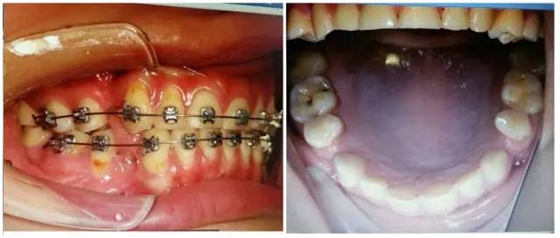

(以下為治療后的照片:患者癥狀得到了良好改善。)

足以看出,尖牙保護(牙合)在臨床工作中的重要作用,它是以尖牙為支撐,對其他牙齒起到保護作用。其特點是正中關系(牙合)與正中(牙合)協(xié)調(diào);側方咬合運動時,工作側只有尖牙保持接觸非工作側牙齒不接觸;在作前伸咬合運動時,上下頜前牙切緣相對接觸,后牙不接觸。尖牙具有適合制導的舌面形態(tài),可使用(牙合)力趨于軸向;牙根長且粗大,支持力強;尖牙位居牙弓前部,在咀嚼時構成第Ⅲ類杠桿,能抵御較大的咀嚼力;以及尖牙牙周膜感受器豐富,對刺激敏感,能及時調(diào)整反應都是尖牙的有利條件。尖牙形態(tài)的恢復在此例正畸治療中,對前牙、后牙都起到了很好的保護作用,也能保證后期按照標準(牙合)進行(牙合)重建時后牙無干擾。功能在先,美觀在后,權老師為您展示了這樣的治療理念。

要想成為一個合格的(牙合)學醫(yī)生,僅僅局限于處理患者已經(jīng)出現(xiàn)的問題是遠遠不夠的,善于挖掘患者潛在隱患的醫(yī)生才是合格的,細致入微的權老師還在病例中發(fā)現(xiàn)兩個潛在問題,群里的同仁們,來吧,跟著權老師,看圖說問題。